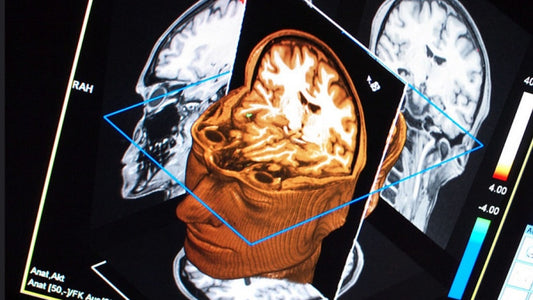

Lo que nadie te dijo de tomar GABA

La producción de GABA es una de las maneras de lograr que nuestras neuronas funcionen perfectamente.

Lo que nadie te dijo de tomar GABA

La producción de GABA es una de las maneras de lograr que nuestras neuronas funcionen perfectamente.